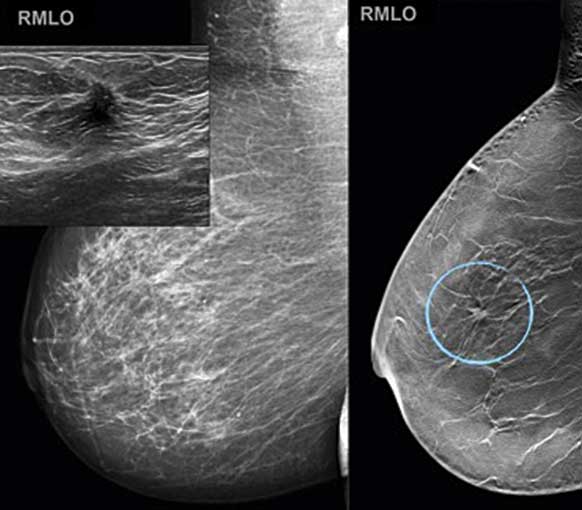

För att nå en likriktad och jämlik cancervård har en nationell cancerplan tagits fram. Detta ämne beskrivs i en artikel av Lars Holmberg och medarbetare. Sophia Zachrisson och medarbetare redogör för hur de dia­gnostiska metoderna förbättrats med högre sensitivitet och bättre bilddiagnostik samt nya teorier kring individualiserad screening.